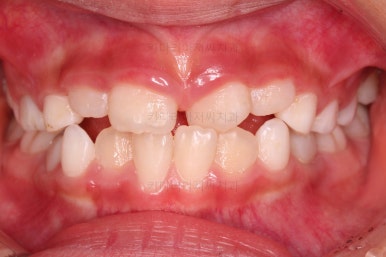

부산어린이반대교합 전후사진을 비교해 볼게요.

4개월만에 원하는 목표를 달성했고 충치도 다 치료했고 무사히 이민을 가실 수 있었답니다.

반대교합만 고쳐준 것이 아니라 기왕 하는김에 치열을 가지런히 해줬고요.

(아래 치열은 장치를 부착해주지도 않았는데 자연스럽게 처음보다 가지런해졌죠? ^^)